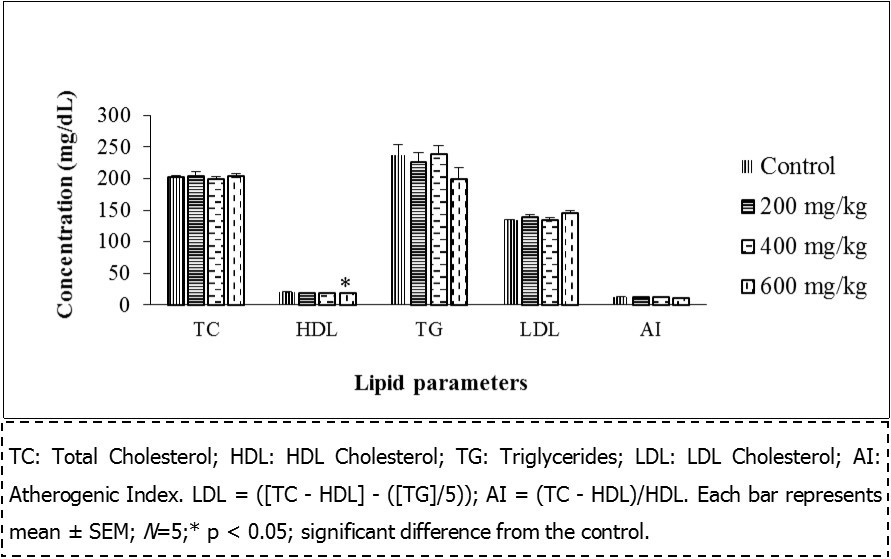

Lipid Profile

As shown in Figure 1, administration of the extract for 28 days in female rats did not alter the lipid profile except for a reduction of HDL cholesterol at a dose of 600 mg/kg. (From 20.08 ± 0.67 to 18.2 ± 0.32, p ˂ 0.05). Whereas this administration had no effect on the lipid profile of the male rats (Figure 2).

Serum cholesterol and triglycerides are largely regulated via synthesis in the liver. Changes in the levels of these lipids could give information on the predisposition of the heart to cardiovascular diseases 35. The extract did not have any significant effect on the triglyceride level while HDL cholesterol was altered at the highest dose of 600 mg/kg in females. The decrease observed in the HDL cholesterol level at the highest dose (600 mg/kg) proposes the incapability of the extract to stimulate the synthesis or interfere with the feedback mechanism associated with this organ, although the mechanism of action was not justified in this study. However, it could be suggested that the extract may not predispose the animals to heart diseases, except at the highest dose. Moreover, Etame et al. 36 also found a decrease in HDL cholesterol, serum glucose, total bilirubin and transaminases activity in both sexes at 200 mg/kg with a stem bark methanol extract of HM after 28 days of administration.